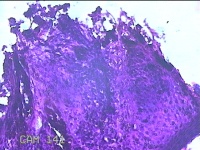

后颈部结节

性别

女

年龄

25岁

临床诊断

皮下结节

一般病史

发现后颈部“黑痣”20余年,伴近日局部瘙痒不适。

标本名称

大体所见

灰白粉红色带皮肤结节0.8x0.7x0.3cm一个,表面糜烂,切开结节呈实性,切面灰白粉红色,质软。

皮内痣